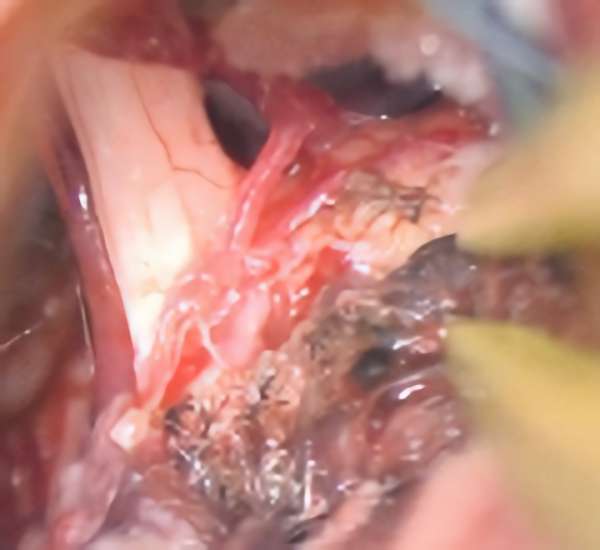

'19年5月

30代

富永/久貝

右中小脳脚 出血再発

SM 3(S1,E1,V1)

米国の病院

No.359 モニタリング

No.359 手術前

No.359 手術中

No.359 手術後

出血既往があり。2回の手術前血管内手術の後に、

Lateral transpeduncular approachにより再々出血予防を目的に

摘出手術を行う。完全摘出であることを確認した。

手術による合併症や後遺症なしで退院した。経過良好。